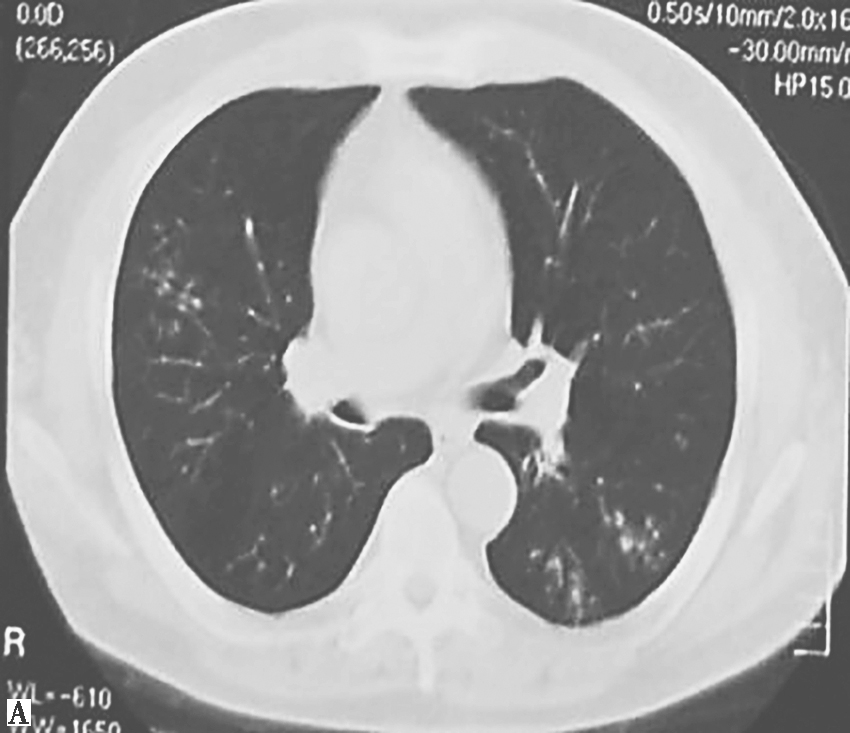

4.胸部CT表现为弥漫性细支气管炎、细支气管扩张(图1)。

图1 胸部CT表现(2011-12-28)

胸部CT显示双肺多发支气管壁增厚、管腔扩张,多发小叶中心性小结节影